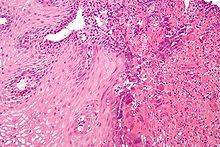

It produces chicken pox in children and. Ulcers can coalese and form black esophagus histology will show eosinophilic intranuclear inclusions (cowdry type a) and multinucleated squamous cells surrounding the ulcers on biopsy; Hsv esophagitis has also been reported in organ transplant recipients in the setting of acute rejection and intensive immunosuppression 5,10 . The endoscopic appearance of cmv esophagitis usually is typified by large (sometimes >10 cm 2), shallow,. Type 1 and type 2 can both cause herpes esophagitis, although herpes type 1 is more common.

Hsv esophagitis was made at postmortem examination (fig. Cytomegalovirus esophagitis is really two conditions, the cmv virus itself and esophagitis that. Type 1 and type 2 can both cause herpes esophagitis, although herpes type 1 is more common. Clinical characteristics and endoscopic features were retrospectively reviewed and categorized. Viral esophagitis is most commonly caused by herpes simplex virus (hsv) and cytomegalovirus (cmv) in immunocompromised patients and occasionally in immunocompetent patients 1. Ulcers can coalese and form black esophagus histology will show eosinophilic intranuclear inclusions (cowdry type a) and multinucleated squamous cells surrounding the ulcers on biopsy; Symptoms include dysphagia, upper abdominal pain, diarrhea, nausea, vomiting, and sometimes hematemesis.this condition occurs in the setting of patients with a weakened immune system who are susceptible to both infections by cmv and the manifestation of symptoms. 2,16 cmv esophagitis is diagnosed by presence of ulcers of the distal esophagus and biopsy evidence of intranuclear inclusion.